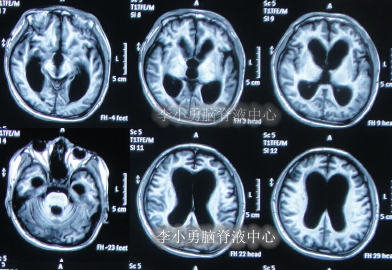

在第2家医院治疗2个月后转至第3家医院天津某军队医院,分别于2012年2月21日和2012年5月23日进行了干细胞移植,其中在第3家医院治疗前曾查头部MRI示脑室仍扩张(图-11)。

图-11:2012年2月22日头部MRI

在第3家治疗半年的时间内,继续给予高压氧治疗,但病情仍未见好转,且不断加重:频繁间断高热,意识模糊,大小便失禁,肢体刺激后才有反应,其中于2012年9月4日查头部MRI示仍脑积水(图-12)。

图-12:2012年9月4日头部MRI